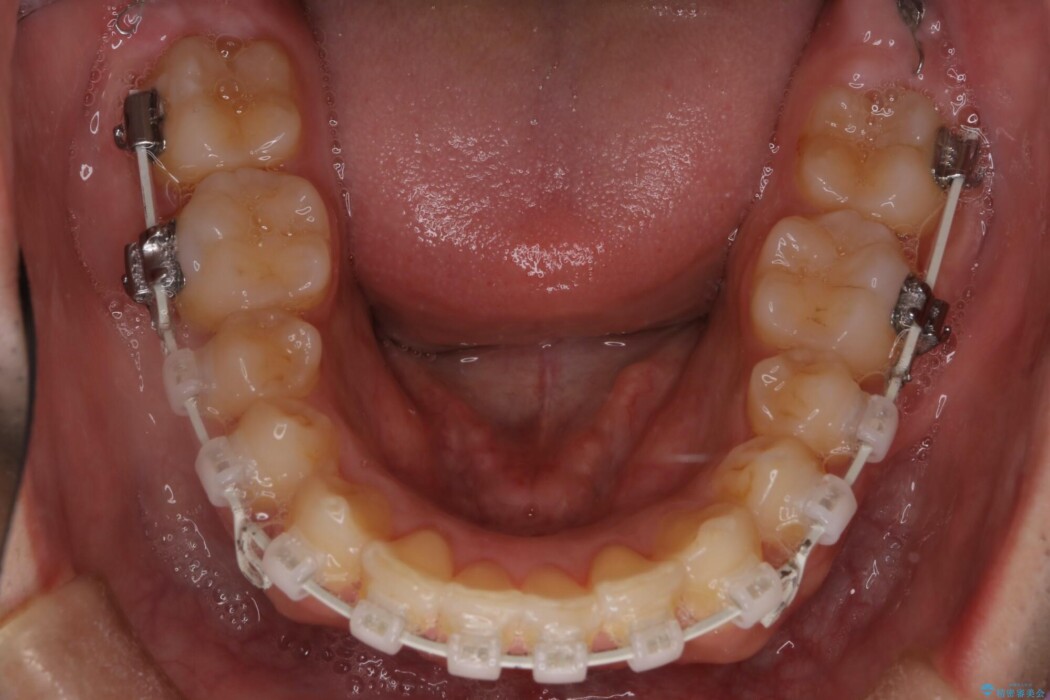

重度の叢生を審美ワイヤー装置で整える

歯列のガタガタさをなおしたいとのことで来院されました。

比較的重度の叢生であり整えるためのスペースが足りなかったため抜歯を行うことで確保し、ワイヤー装置にて配列を行いました。

当初はインビザラインでの治療をしていましたが、装着時間の確保が出来ないことからワイヤー矯正治療へ移行しています。

特に奥歯の捻転がひどく、整った歯列となるまでに時間は要しましたが、きれいな仕上がりに患者様には大変ご満足いただけました。